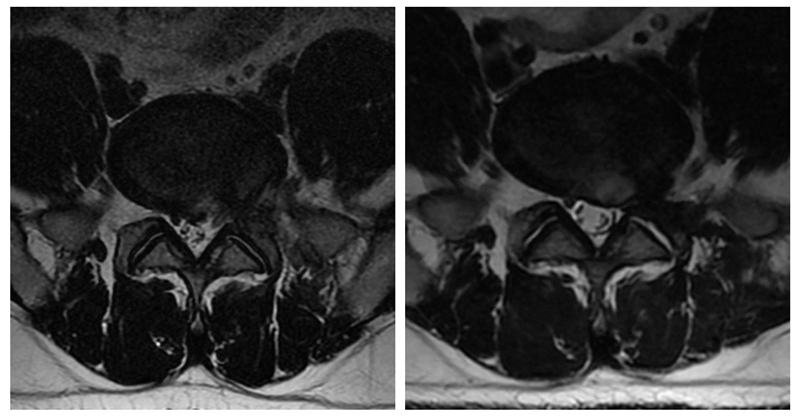

2、术后复发

术后复发的定义为术后超过6个月的无痛期后同一节段的椎间盘,于同侧或对侧再次出现突出造成患者症状,并经影像学证实。文献报道复发率约为5.7-10.6%,造成复发的因素众说纷纭,目前普遍认为认为老年、肥胖、Modic改变是术后复发的危险因素。

因术中对椎间隙的处理无法像融合手术那么彻底,还要考虑术后间隙塌陷、间盘退变加重等因素,残留的髓核组织可于纤维环破口处再次脱出造成症。对于术后复发的处理,如规律的保守治疗无效可再次行手术治疗(内镜、开放手术均可),但如再次行PTED治疗,要警惕局部解剖结构辨识不清、瘢痕组织形成、组织粘连等问题,需经验较丰富的医师完成手术。